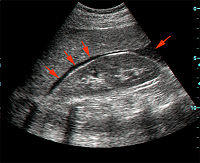

A positive FAST - fluid (black stripe, indicated by red arrows) within Morison's pouch.

FAST is most useful in trauma patients who are hemodynamically unstable. A positive FAST result is defined as the appearance of a dark ("anechoic") strip in the dependent areas of the peritoneum. In the right upper quadrant this typically appears in Morison's Pouch (between the liver and kidney). This location is most useful as it is the place where fluid will collect with a supine patient. In the left upper quadrant, blood may collect anywhere around the spleen (perisplenic space). In the pelvis, blood generally pools behind the bladder (in the rectovesicular space). A positive result suggests hemoperitoneum; often CT scan will be performed if the patient is stable[18] or a laparotomy if unstable. In those with a negative FAST result, a search for extra-abdominal sources of bleeding may still need to be performed.